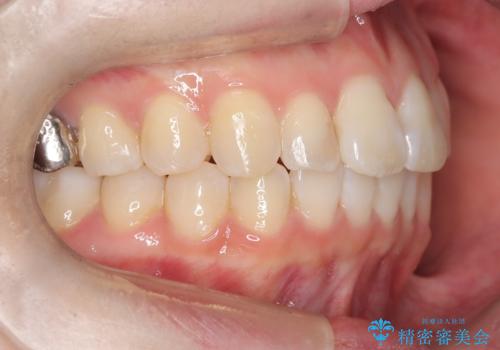

前歯のガタつきをマウスピース矯正で改善

- 前歯のガタツキが気になると来院されました。

奥歯の噛み合わせは綺麗に噛んでいたため、前歯の叢生(でこぼこ)に集中して治療するように計画しました。